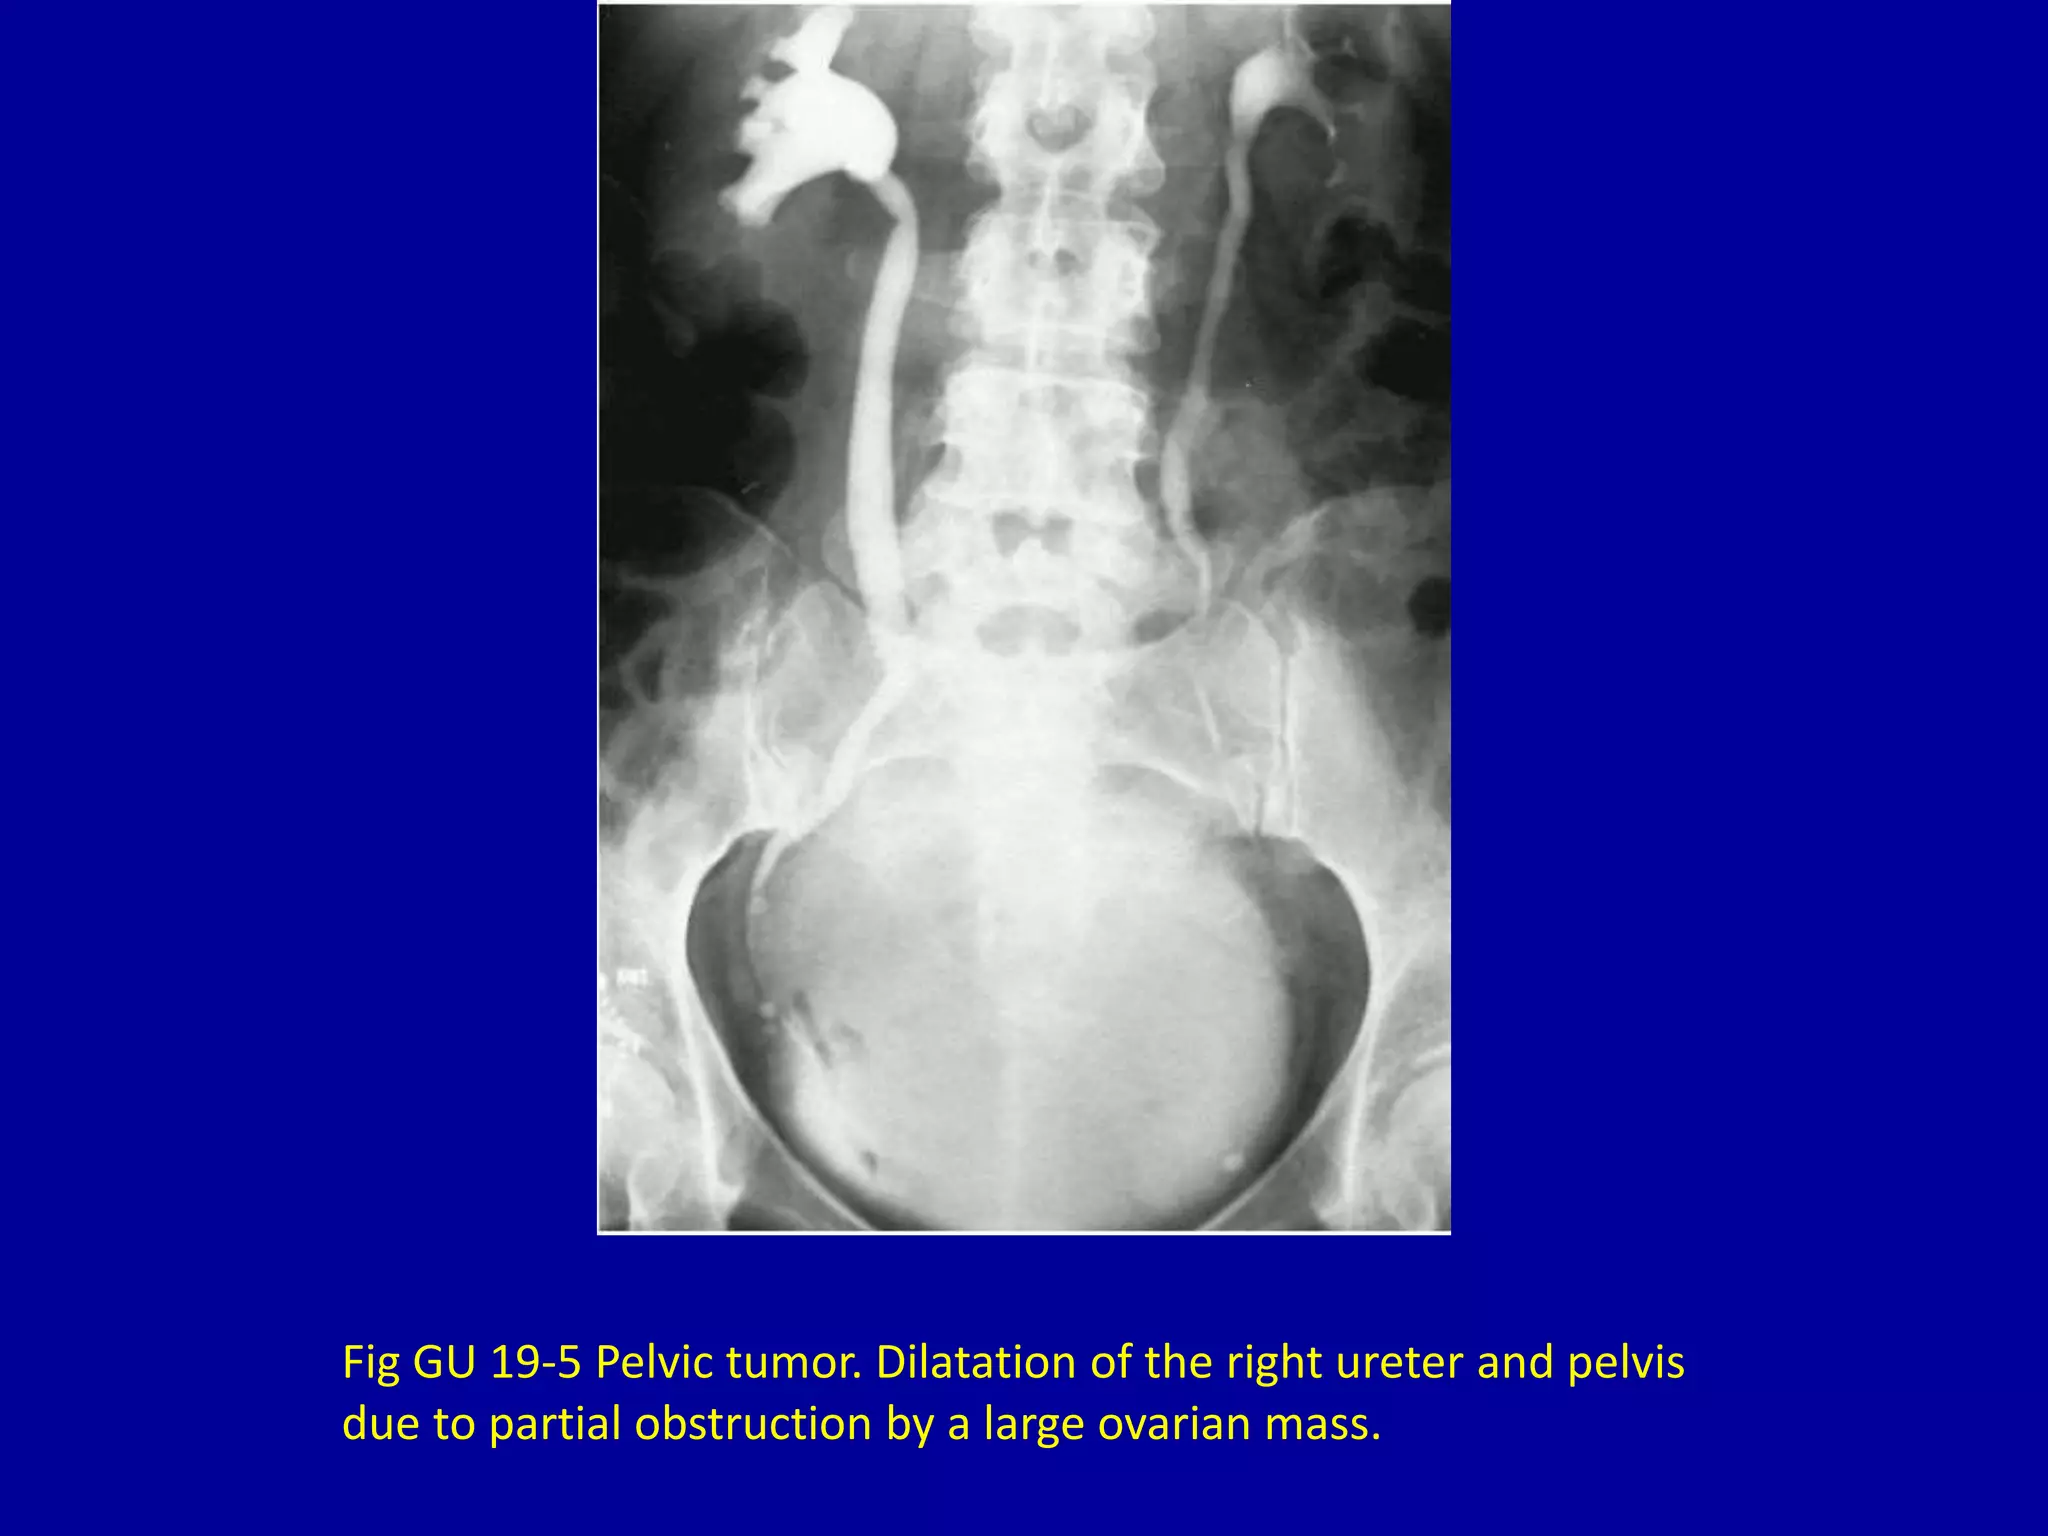

Fig GU 19-5 Pelvic tumor. Dilatation of the right ureter and pelvis

due to partial obstruction by a large ovarian mass.

Fig GU 19-5Pelvic tumor. Dilatation of the right ureter and pelvis due to partial obstruction by a large ovarian mass.